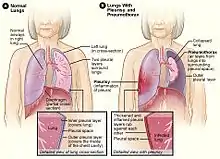

| Figure A shows normal anatomy. Figure B shows lungs with pleurisy in the right lung, and a pneumothorax of the left lung. | |

Pleurisy, also known as pleuritis, is inflammation of the membranes that surround the lungs and line the chest cavity (pleurae).[1] This can result in a sharp chest pain while breathing.[1] Occasionally the pain may be a constant dull ache.[5] Other symptoms may include shortness of breath, cough, fever, or weight loss, depending on the underlying cause.[5] Pleurisy can be caused by a variety of conditions, including viral or bacterial infections, autoimmune disorders, and pulmonary embolism.

The most common cause is a viral infection.[2] Other causes include bacterial infection, pneumonia, pulmonary embolism, autoimmune disorders, lung cancer, following heart surgery, pancreatitis and asbestosis.[2] Occasionally the cause remains unknown.[2] The underlying mechanism involves the rubbing together of the pleurae instead of smooth gliding.[1] Other conditions that can produce similar symptoms include pericarditis, heart attack, cholecystitis, pulmonary embolism, and pneumothorax.[3] Diagnostic testing may include a chest X-ray, electrocardiogram (ECG), and blood tests.[3][6]

Pneumothorax

Air or gas also can build up in the pleural space. This is called a pneumothorax. It can result from acute lung injury or a lung disease like emphysema. Lung procedures, like surgery, drainage of fluid with a needle, examination of the lung from the inside with a light and a camera, or mechanical ventilation, also can cause a pneumothorax.

The most common symptom is sudden pain in one side of the lung and shortness of breath. A pneumothorax also can put pressure on the lung and cause it to collapse.